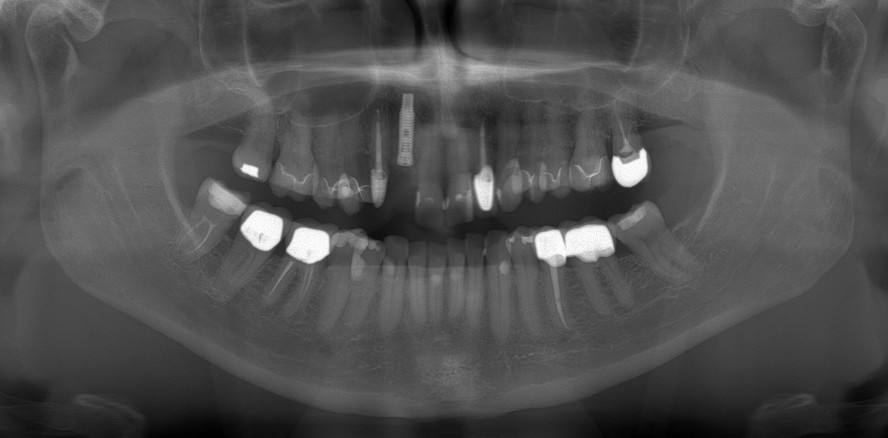

Die Daten zum Knochenverlust wurden anhand von OPG-Auswertungen erhoben.

In der vorliegenden retrospektiven Studie wurden 100 Implantate der Firma BIOMET 3i® bei 100 Patienten in einer niedergelassenen Zahnarztpraxis ausgewertet. Es wurden selbstschneidende zylindrische Vollschraubentitanimplantate der Längen 8,5; 10; 11,5; 13; 15 und 18mm mit den Durchmessern 3,25; 3,75; 4; 5 und 6 mm verwendet. Mit 67 Implantaten war der Anteil der 4 mm-Implantate am höchsten. Die Implantate mit 11,5 mm Länge waren mit 41 Prozent am häufigsten vertreten. Andere Studien zeigen, dass der Anteil der Implantate, je nach Hersteller, von 3,5 mm bis 5 mm Durchmesser sowie Implantate mit Längen von 10 bis 13mm eine häufige untersuchte Verteilung darstellen.81,31,105,113 Das Alter der Patienten unserer Studie lag bei 22 bis 88 Jahren, wobei der Mittelwert 58,95 Jahre betrug. Ähnliche Konstellationen der Altersverteilung finden sich auch in den Studien anderer Autoren.34,118 In der Studie wurden 43 männliche und 57 weibliche Patienten untersucht. Auch dies entspricht in etwa der Verteilung anderer Studien.118,25